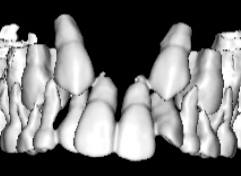

治療前

治療開始時